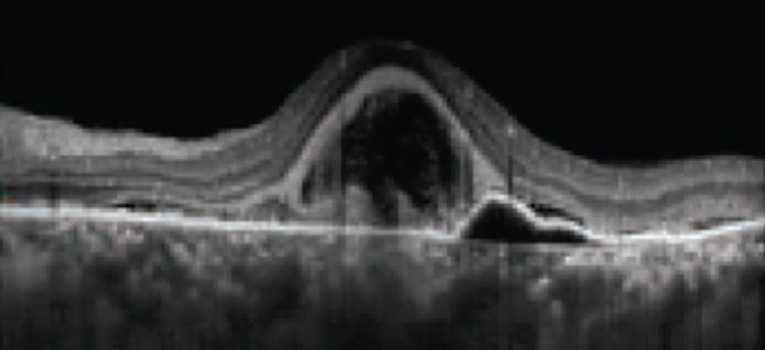

Die Fovea Friendly™ MicroPulse® Lasertherapie erlaubt auch die Behandlung von schwierigen Fällen, in denen die Fovea mit involviert ist. Nach einer MicroPulse® Laserbehandlung kommt es zu keinen morphologischen Veränderungen, der Zerstörung von neurosensorischen Netzhautschichten, weder im OCT, der Angiographie, Autofluoreszenz, oder im Funduskop, nachweisbar. Es entstehen keine typischen Lasernarben und Skotome mit entsprechenden Visus-Beeinträchtigungen.

VA 20/25 CMT 204μm

MicroPulse® Laser Behandlung über der Fovea nach chronisch bullöser RCS. Keine Zerstörung von neurosensorischen Netzhautschichten, keine Lasernarben-Skotome

Lasern über der Fovea ist mit dem Iridex MicroPulse® Laser sicher und kann bei entsprechender Indikation mit in die Behandlung eingeschlossen werden (FDA-zugelassen). Die thermische Stimulation des RPE dient als biologischer Schlüsseltrigger für den Abbau von Flüssigkeitsansammlungen einer ödematösen Retina. Entstehende Heat Shock Proteine haben eine stimulierend proliferierende und protektive Wirkung und bewirken eine „Upregulation“ von angiogenen Inhibitoren sowie eine „Downregulation“ von VEGF.